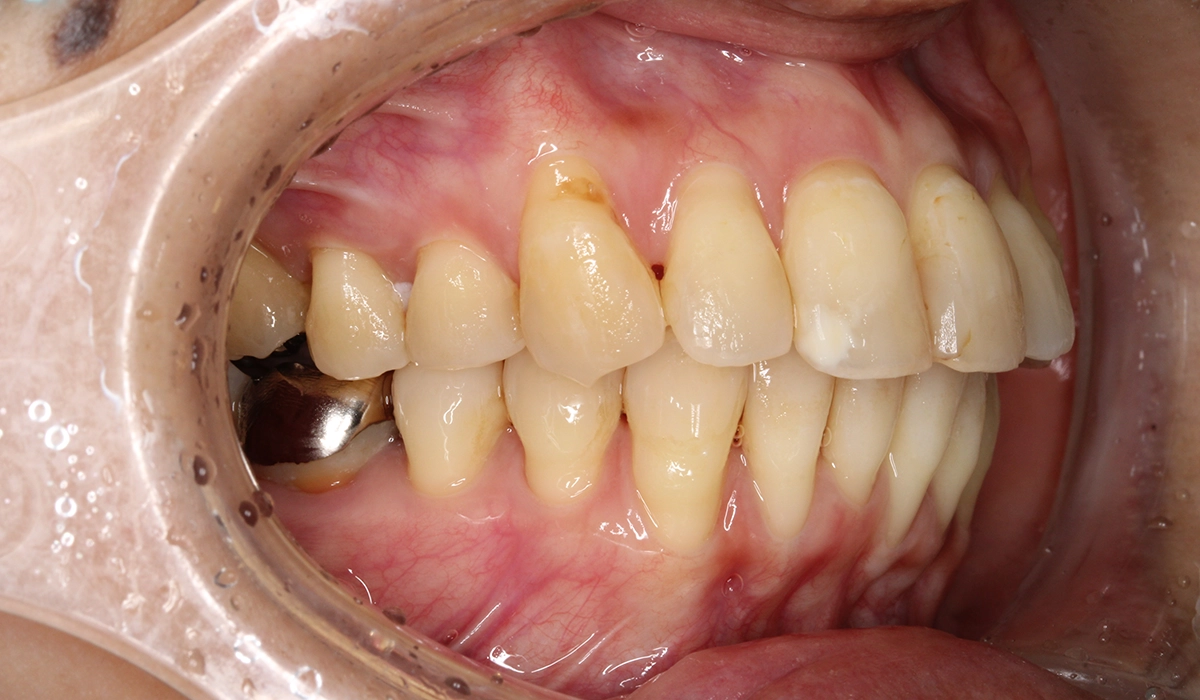

術前:左側

| 治療内容 | 患者様は全体的な歯のがたつきを気にされており、矯正検査後Ⅰ級叢生と診断。抜歯適応症例だが患者希望により歯肉退縮を許容したうえで非抜歯で仕上げている。 |

| リスク・副作用 | ・協力度(装着時間、来院、顎間ゴムの使用など)が治療期間や結果に影響します。 ・事前のシミュレーションのゴールを目指し歯を移動させていく治療法ですが、歯の動きには個人差があるため確実に結果を保証するものではありません。 ・食事に時間がかかり、歯ごたえのあるものが食べにくくなります。 ・歯の移動に伴う痛みや装置による口内炎、関節音、閉口障害、頭痛、耳鳴り、筋の硬直などが生じることがあります。 ・歯の動きに伴い、歯肉退縮や歯根吸収が生じることがあります。 ・ブラックトライアングル(三角形の隙間)ができることがあります。 ・歯の動かし方によっては詰め物やかぶせ物を外す可能性があります。外した場合は矯正終了まで仮の材料を入れ、終了後に新たに作り直す必要があります。 |